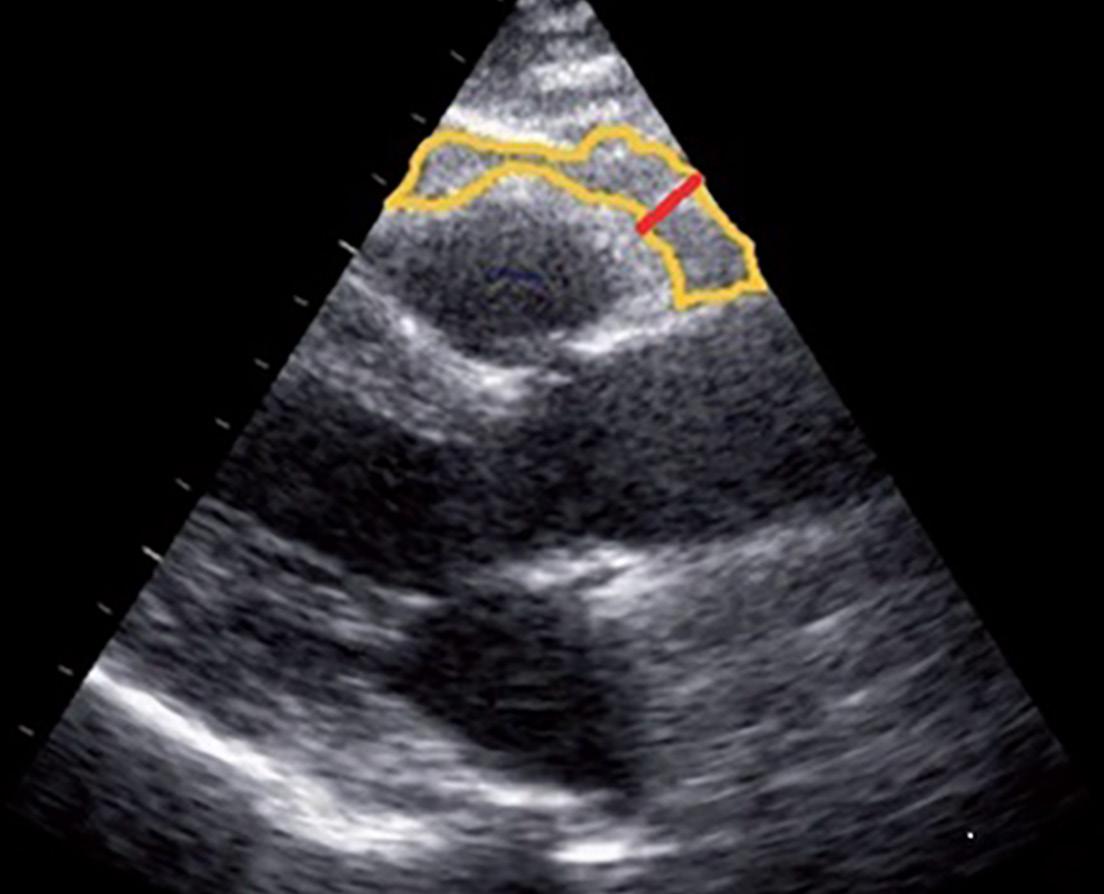

(Top left) Dr. Iacobellis’ group first discovered the presence of the receptors of the GLP-1 analogs (shown by the red arrows) within the epicardial adipocytes, highly suggesting that the beneficial cardiovascular effects of the GLP-1 analogs are mediated by epicardial fat. (Top right) Dr. Iacobellis invented a technique to measure the epicardial fat thickness (within the yellow line) using standard and not invasive ultrasound.

But in 2003, Dr. Iacobellis discovered that a standard ultrasound machine could do the job in the convenience of an outpatient clinical setting. Thanks to this inexpensive, noninvasive procedure he developed, healthcare professionals can not only detect and measure epicardial adipose tissue (EAT) but also predict and prevent diseases often associated with it.